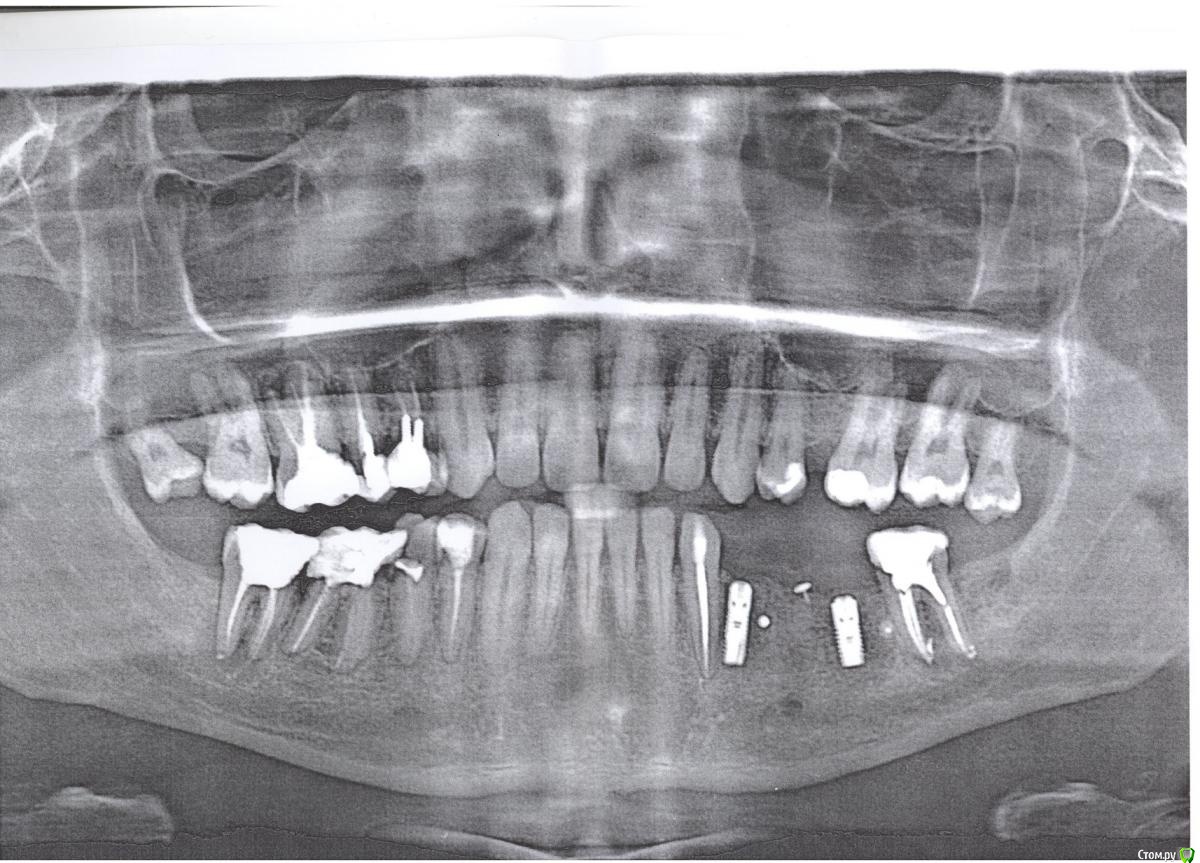

eugen.berend Опубликовано 17 января, 2015 Поделиться Опубликовано 17 января, 2015 (изменено) Здравствуйте,Есть проблема с 33 зубом. В мае 2012 мне поставили мостовой протез 33-35-37. Через какое-то время у меня онемела часть губы рядом с 33 зубом и от постукивания по его коронке появилось странное ощущение - не знаю как описать - как будто отдаёт в корень, не болезненное, но ощутимое. Не могу точно сказать, были или нет такие ощущения до установки протеза.Далее в июле 2014 мостовидный протез мне убрали, временно оставив коронку на 33 зубе, т.к. жалоб на него не было.В сентябре 2014 в один из дней зуб внезапно невыносимо разболелся. Я побежал в клинику, врач снял коронку, удалил пульпу и пролечил канал. При этом анестезия совершенно не подействовала, так что пришлось терпеть китайские пытки. После пролечивания ощущения от постукивания ослабли, но не прекратились вовсе. При прикосновении к щеке в области этого зуба металлическим предметом - странное ощущение, как от очень слабых электрических импульсов.Я задал вопрос насчёт этого зуба лечащему меня ортопеду. Поинтересовался, что это такое вокруг корня - воспаление? Он сказал, что там всё ок, что то, что я принял за воспаление - это периодонт, что зуб будет протезирован коронкой на штифто-культевой вкладке, в числе прочих.НО, терапевту этот вопрос я ещё не задавал, следующая консультация у меня только в среду. Хотелось бы узнать примерно, что меня ждёт.Я читал о травматическом периодонтите - когда периодонт воспаляется из-за постоянной травмирующей нагрузки зуба, например, некорректно изготовленным протезом. Это оно? Сильно сложно лечить, есть ли вероятность потери зуба?Снимок октября 2014, завтра могу сделать прицельный снимок. Изменено 17 января, 2015 пользователем eugen.berend Ссылка на комментарий

eugen.berend Опубликовано 28 января, 2015 Автор Поделиться Опубликовано 28 января, 2015 http://s019.radikal.ru/i615/1501/0a/c9994ce0abdf.jpghttp://s49.radikal.ru/i125/1501/bd/e20009e103fc.jpg Ссылка на комментарий

IvanK Опубликовано 30 января, 2015 Поделиться Опубликовано 30 января, 2015 Думаю, что нужно проверить имплантат Ссылка на комментарий

red_butler Опубликовано 31 января, 2015 Поделиться Опубликовано 31 января, 2015 Думаю, что нужно проверить имплантатэто мягко сказано. eugen.berend как можно скорее покажитесь своему хирургу 1 Ссылка на комментарий

IvanK Опубликовано 6 февраля, 2015 Поделиться Опубликовано 6 февраля, 2015 А что там такое? проблема в имплантате Ссылка на комментарий

eugen.berend Опубликовано 6 февраля, 2015 Автор Поделиться Опубликовано 6 февраля, 2015 Отправлял хирургу снимок, он сказал, что на оптг уровень кости норм, а прицельный снимок, похоже, недоэкспонирован. Ортопед также осмотрел меня, сказал, что всё ок. Но очного приёма у хирурга ещё не было - будет через неделю, он вообще собирался мне уже формирователи ставить. Я напишу по результату. Ссылка на комментарий